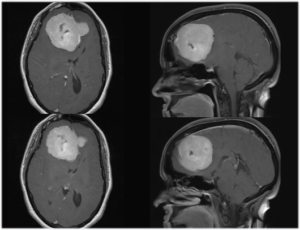

Brain Tumors

Intracranial and Extracranial Tumor Embolizations

Various tumors in the brain, head, neck, and spine can be treated pre-operatively with embolization to reduce the risk of bleeding during open surgery.

The list of tumors amenable to this therapy is very broad and includes meningiomas, glomus tumors, paragangliomas, nasopharyngeal angiofibromas, as well as metastatic cancerous tumors from the lung, breast, kidney, skin, and bowel. The procedure involves selection of the small arteries that supply blood flow to the tumor followed by the injection of small particles to reduce blood flow and induce ischemia within the tumor tissue.